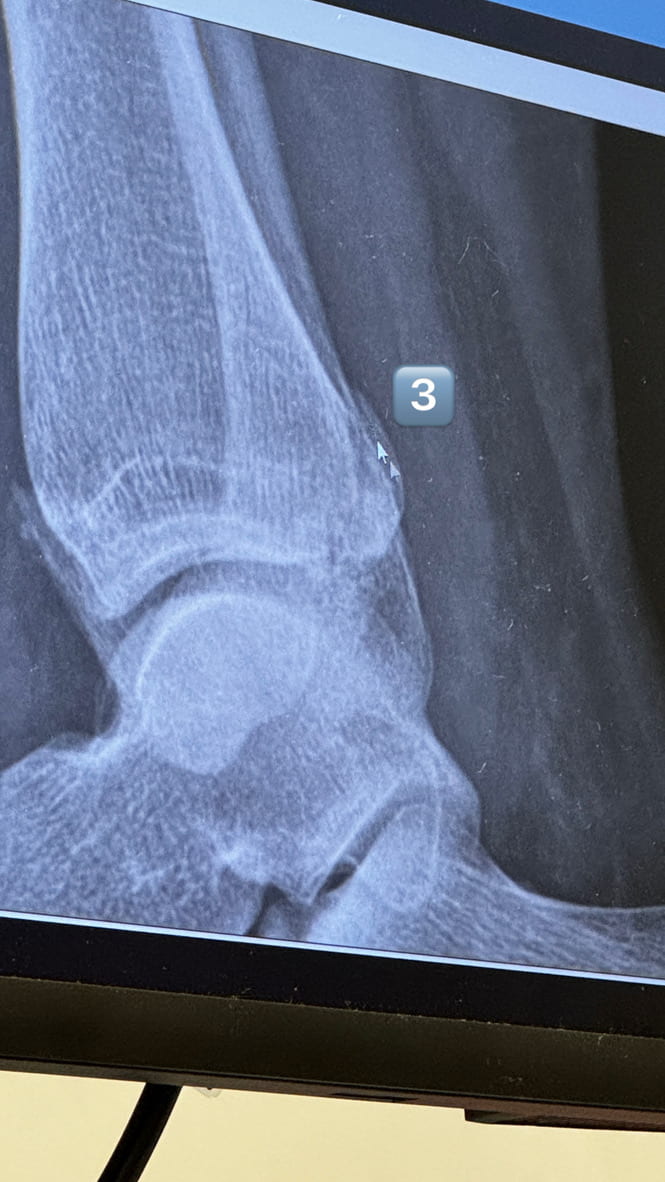

Above: my 3 breaks

Eventually, about 3am I think, the images came back - 3 breaks. They said I’d see a consultant who would decide it if just needed casting or of I would need surgery. ‘SURGERY!” I shouted (literally shouted) in surprise. The nurse looked at me and said something like “yes, you’ve done quite a job here!” (smiling I might add!).